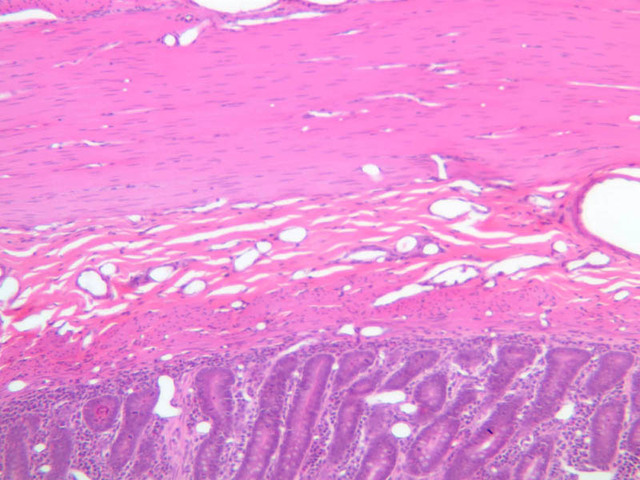

Delicate lymphatic channels consisting of capillaries and larger vessels are spread throughout the body. Periodically along these channels are small collections or complex aggregations of lymphocytes associated with delicate meshworks of reticular tissue. Approximately 50% of the plasma volume is lost each day to the tissues so a major function of the lymphatic channels is to collect fluid from tissue spaces and return it to the blood; but in transit, the plasma-like fluid is filtered through lymphoid tissue. Lymphatic vessels and tissue constitute a very widespread and extremely important filtering system between the body tissues and the bloodstream, and they prevent the spread of infectious agents by the vascular system. Lymphatic capillaries and vessels also transport proteins and other substances that leak from blood capillaries back to the blood via the thoracic and right lymphatic ducts, and in the intestines they are a principal pathway for carrying fats from the absorptive cells of intestinal villi to the bloodstream. Lymph capillaries are readily seen, but often go unnoticed in sections of tissue where they may be mistaken for fixation shrinkage artifacts. Examine intestinalthe villi in section B-12 and find the blind-ending capilliform vessel that lies in the axis of the villus (B-12, H&E [10x-labeled, 20x, 40x-labeled] [10x, 20x-labeled, 40x] [10x, 20x, 40x-labeled]; B-15, H&E [2.5x, 10x, 20x, 40x] [2.5x, 10x. 20x, 40x]). This is a lymph capillary known as a lacteal (because of its milky appearance after a fatty meal). Note its thin endothelial wall and its irregular lumen, common features of lymphatic vessels. Lacteals, in their passage to deeper-lying lymphatic vessels, usually pass through diffuse collections of lymphoid tissue. Lymphatic vessels larger than capillaries are similar in structure to comparable-sized veins, but have thinner walls. Thus, try to find vessels in the intestinal submucosa that seem to be venules, but have no cellular content. These are likely lymphatic vessels. Periodically along the lymphatics (and the venules also) valves occur, which are infoldings of the intimal layer of the vascular wall. These structures prevent backflow of lymph (or blood) ensuring a uni-directional flow. Lymphatic vessels are difficult to find and valves are rarely observed (i.e., don't spend too much time trying to identify these structures).

Diffuse Lymphatic Tissue and Nodules

The visceral walls have concentrations of lymphoid tissues that comprise the body's filters against foreign organisms that attempt to enter by way of the alimentary, urinary, or respiratory tracts. The lamina propria is a layer of connective tissue underlying the epithelium of mucous membranes; lymphatic tissue is often found in the lamina propria. This lymphatic tissue can assume three forms; 1) diffuse lymphatic tissue, 2) solitary lymphatic nodules, and 3) aggregated lymphatic nodules. The simplest arrangement of lymphoid tissue occurs as diffuse patches of lymphocytes scattered in the lamina propria of the walls of visceral organs. When a patch becomes activated by antigens or foreign organisms, it takes on the appearance similar to a nodule in the cortex of a lymph node (see below). These nodules are not encapsulated and simply occur in the visceral wall as an accumulation of lymphocytes, macrophages, and plasma cells embedded in reticular tissue. Eosinophilic leukocytes are frequently seen.

Examine sections B-12 (jejunum, H&E [2.5x, 10x-labeled, 20x, 40x]); B-16, ileum, H&E [2.5x-labeled, 10x, 20x]; B-18, ileum, H&E [2.5x, 10x-labeled, 20x, 40x]; B-20, appendix, H&E [2.5x, 10x-labeled, 20x, 40x-labeled]) and find examples of diffuse lymphatic tissue. Solitary nodules of lymphoid tissue as well as diffuse lymphoid tissue can be found almost anywhere along the gastrointestinal system (this is sometimes called GALT, gut associated lymphoid tissue). The most noted areas with aggregated nodules are found in ileum—Peyer’s Patches (slide B-18, H&E [2.5x-labeled, 10x-labeled, 20x, 40x] [2.5x, 10x, 20x, 40x]), and appendix (slide B-20, H&E [2.5x, 10x, 20x, 40x] [2.5x, 10x,20x, 40x] [2.5x-labeled, 10x, 20x-labeled, 40x]). Peyer's Patch consists of aggregated nodules of lymphoid tissue. Compare the appearance of Peyer's patches to the lymphoid tissue in the appendix. In the appendix, the lymphoid tissue of the appendix appears as a continuous ring of lymphatic tissue in the lamina propria. What features differentiate the appendix from the Ileum?